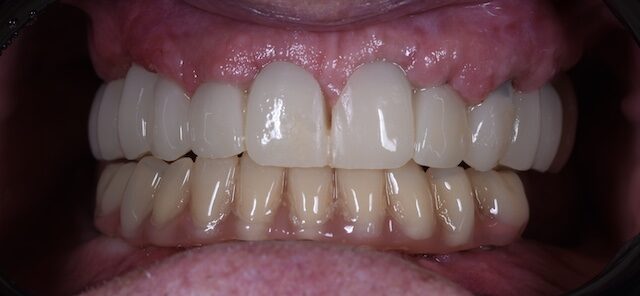

Az implantátumok csontosodása után készül el a végleges fix, csavarozható, cirkon-kerámia hídpótlás. A csavarozható pótlások előnye, hogy bármilyen sérülés esetén a pótlás könnyen eltávolítható és javítható, nem kell levágni és újra elkészíteni. Ezáltal ez egy sokkal költséghatékonyabb megoldás.

Ezen kezelések eredményeként 1 hét leforgása alatt egy kedves páciensünk életét tudtuk jobbá tenni. Újra tud bátran mosolyogni és jóízűen enni és a beszéde is könnyebb és érthetőbb.